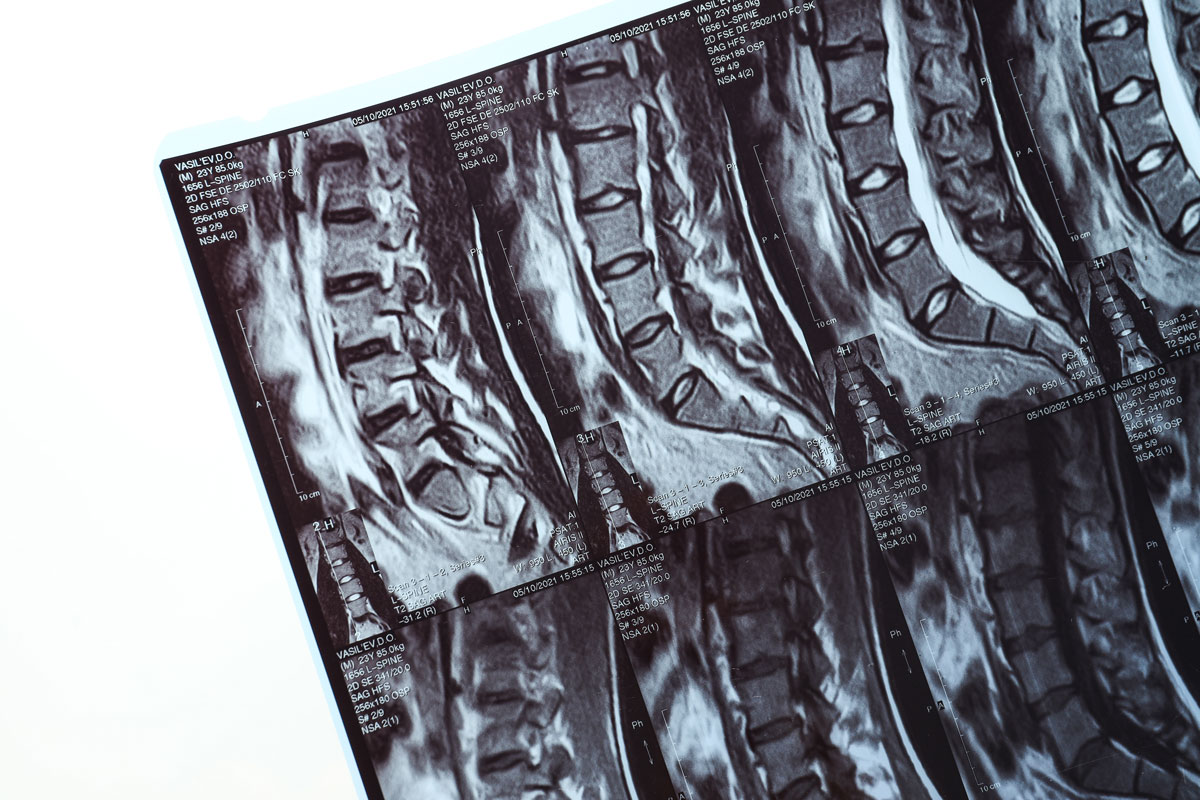

Radio frequency ablation, often referred to as RFA, is a minimally invasive procedure that uses carefully controlled heat to interrupt pain signals from targeted nerves.

The procedure is performed using advanced imaging guidance to ensure precision.

A small needle is placed near the nerve responsible for the pain. Controlled heat is then delivered to interrupt the nerve’s pain signaling ability.